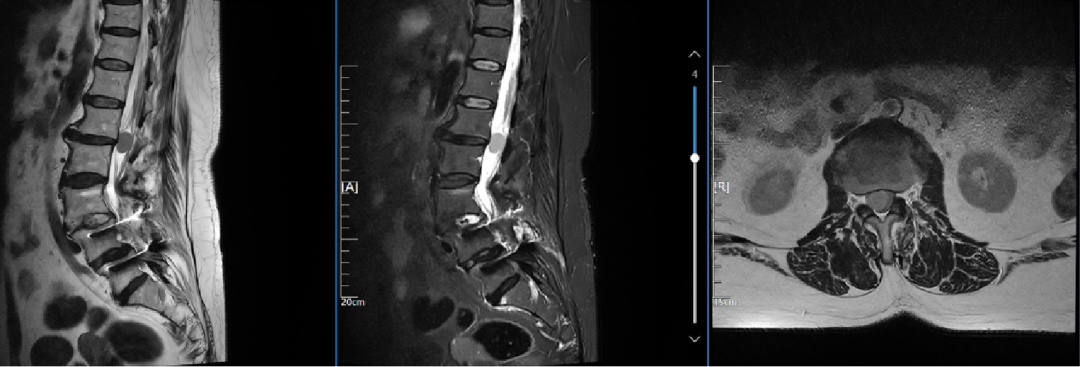

曹鹏医生进行了细致的体格检查,结合影像资料,发现李阿婆不止有脊柱肿瘤,同时合并严重脊柱侧弯。加之她几年前已经做过腰椎后路减压融合内固定术,再次手术确实有难度。

术前X-RAY显示严重脊柱侧弯,椎管内肿瘤

经过与团队紧锣密鼓的讨论,曹鹏主任医师为李阿婆制定了个性化的微创手术方案。“相比较于开放手术,这种全新的微创手术技术,两个小切口可以同时解决融合、固定和肿瘤切除三个难题,伤口小愈合快,并发症也更少。”曹鹏医生说,“由于患者已经做过后入手术,瘢痕形成,神经被瘢痕包裹粘黏。如果再次后路手术,要想把神经分解开,就好比要把完全粘黏在皮肤上的衣服撕开,很容易损伤神经和硬膜。通过OLIF手术,从腰椎侧方入路,我们可以有效避免这些损伤。”

在麻醉科、手术室团队保驾护航下,曹鹏医生团队为李阿婆成功实施手术。因为刀口很小,他需要通过多次透视来精准定位。而且腹部有着腹主动脉 、节段动脉、下腔静脉等大血管,稍有不慎就可能造成大出血,且手术部位紧邻输尿管和交感神经链,要同步做好保护,难度很高。在曹鹏医生精湛的技术和团队通力协作下,历时2个半小时,李阿婆肿瘤顺利切除,一个4.5厘米长,1.4厘米高的超大“融合器”被成功放置,它比普通融合器大了3倍,为患者腰椎提供强有力支撑,手术几乎无出血。